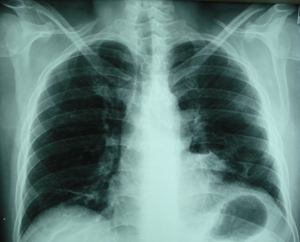

Εικόνα 6

Οπισθιοπροσθία ακτινογραφία του θώρακος, έξι μέρες μετά από την αφαίρεση των κύστεων, την αφαίρεση των σωλήνων παροχέτευσης και προ της εξόδου του ασθενούς από το νοσοκομείο. Πλήρης έκπτυξη του αριστερού πνεύμονος.